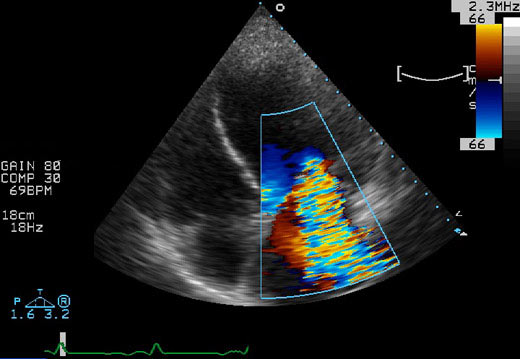

Insuffisance mitrale importante - Chirurgie, anneau mitral percutané, clip mitral ou resynchronisation cardiaque ?

Dr Benoît Fouchet Marseille

Le débat vient d’être réouvert par l’étude EVEREST II présentée par le Dr T. Feldman au congrès de l’ACC.

L’étude EVEREST II est une étude randomisée multicentrique. Dans cette étude, des patients présentent une insuffisance mitrale grade III ou IV entre clip mitral et chirurgie valvulaire mitral.

Le principal critère de jugement se composait des évènements cardiaques majeurs à 30 jours (supériorité) et la survie sans réintervention ni insuffisance mitrale ≥ 2 à 12 mois (non infériorité).

Cette étude